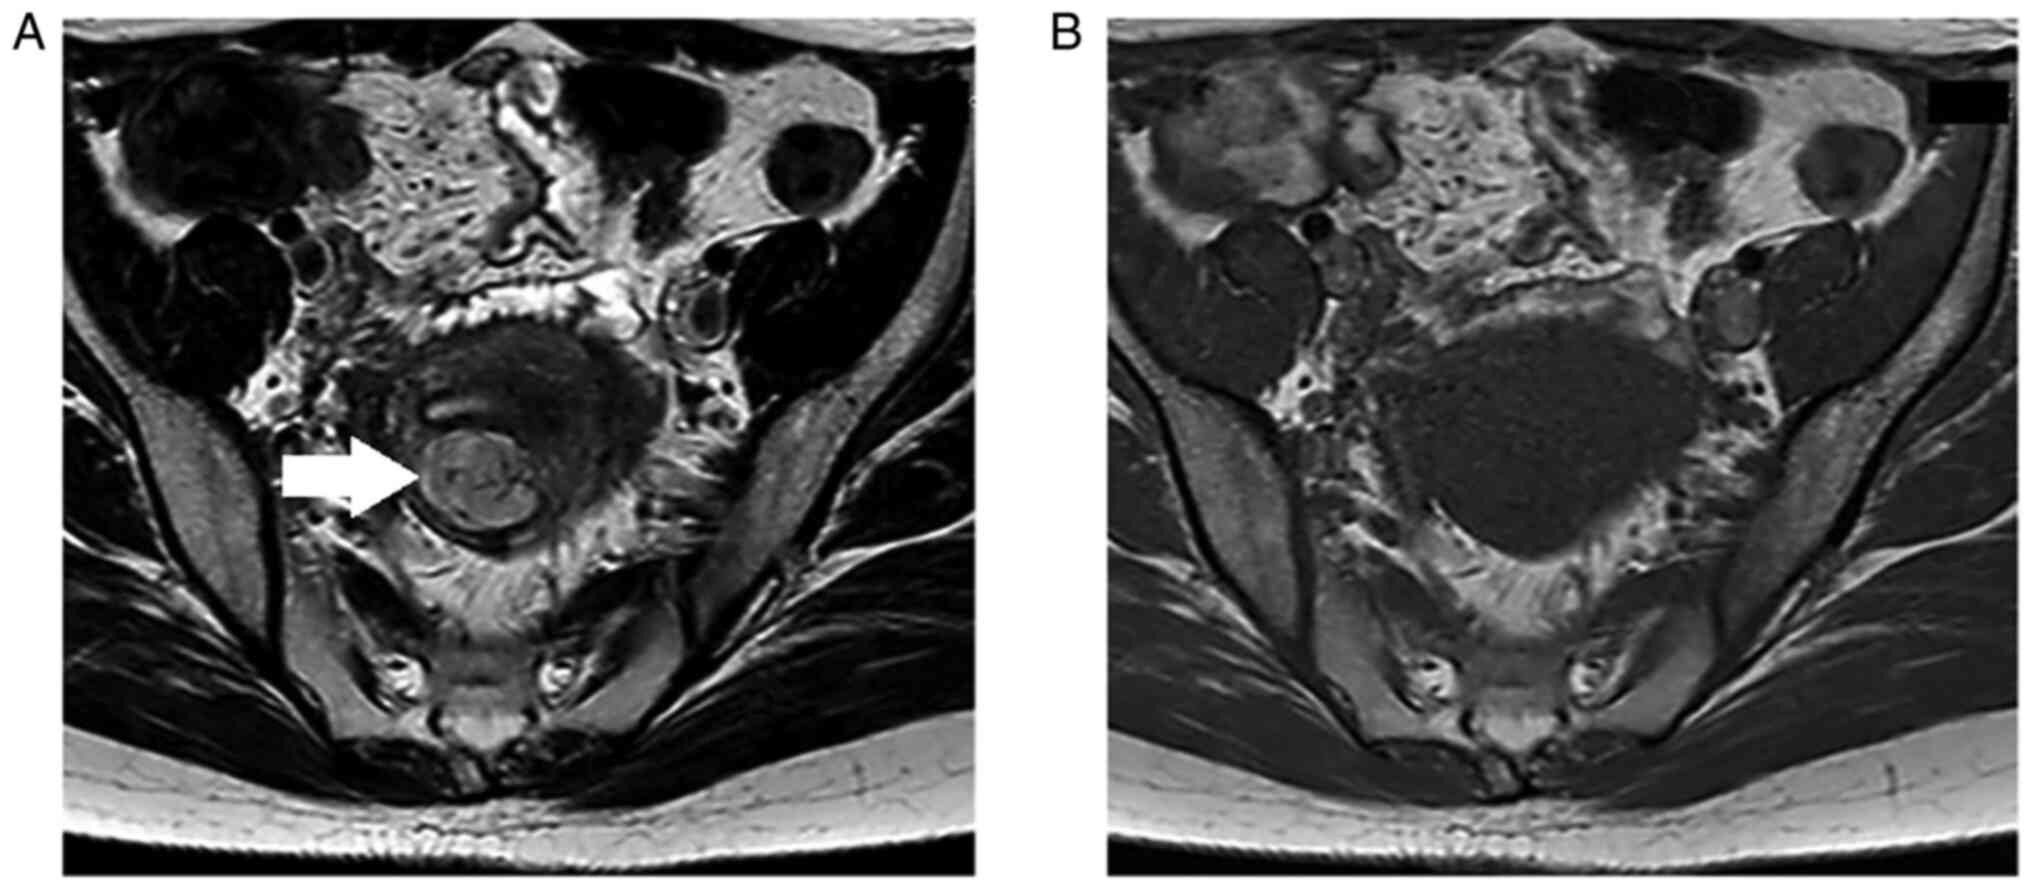

The patient was a 41-year-old, gravida 1, para 1 female. She visited a nearby clinic with complaints of ovulation bleeding and lower abdominal pain, and was referred to Osaka City University hospital due to the presence of a 31x21 mm uterine body mass with an internal hyperechoic region, as identified by transvaginal ultrasonography. MRI findings showed a diffuse high signal of a ~30 mm uterine corpus tumor on T2-weighted images, but a low signal on T1-weighted images (Fig. 1A and B). In addition, since the diffusion-weighted image showed a high signal, but the apparent diffusion coefficient did not decrease, the tumor was not restricted in diffusion and was considered to have few findings suggestive of malignant disease. The protocol for MRI imaging is as follows: TR (time to repeat); 4,000 milliseconds, TE (echo time); 85 milliseconds (Sagittal)/100 milliseconds (Axial), receive bandwidth; 100 Hz, Field of view; 27 cn, Slice thickness; 5 mm, Matrix number; 512x273, b-value; 0-1,000 second/mm2, diffusion measurement time; 108. Blood analysis showed no abnormalities in serum lactate dehydrogenase and CA125 levels. Based on the aforementioned results, it was considered that there were few findings supportive of uterine leiomyosarcoma, and the MRI findings were considered to be different to that of typical uterine leiomyomas. Therefore, it was decided to perform a histological examination by transcervical needle biopsy (needle biopsy).

Figure 1

Magnetic resonance imaging scan from the first visit. The uterine tumor found in the muscular layer of the posterior wall measured about 30 mm in diameter, and showed a diffusely high signal on T2-weighted image and a low signal on T1-weighted image. (A) T2-enhanced axial image. Uterine tumor is indicated by a white arrow. (B) T1-enhanced axial image.